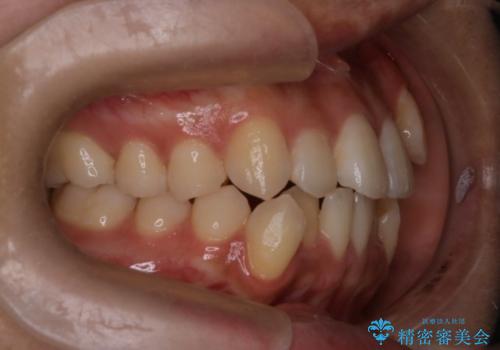

- 八重歯を主訴に来院されました。4番の歯を4本抜歯し、八重歯を並べる計画をたてました。

抜歯をし、スペースを確保したことにより八重歯をきれいに並べることが出来ました。